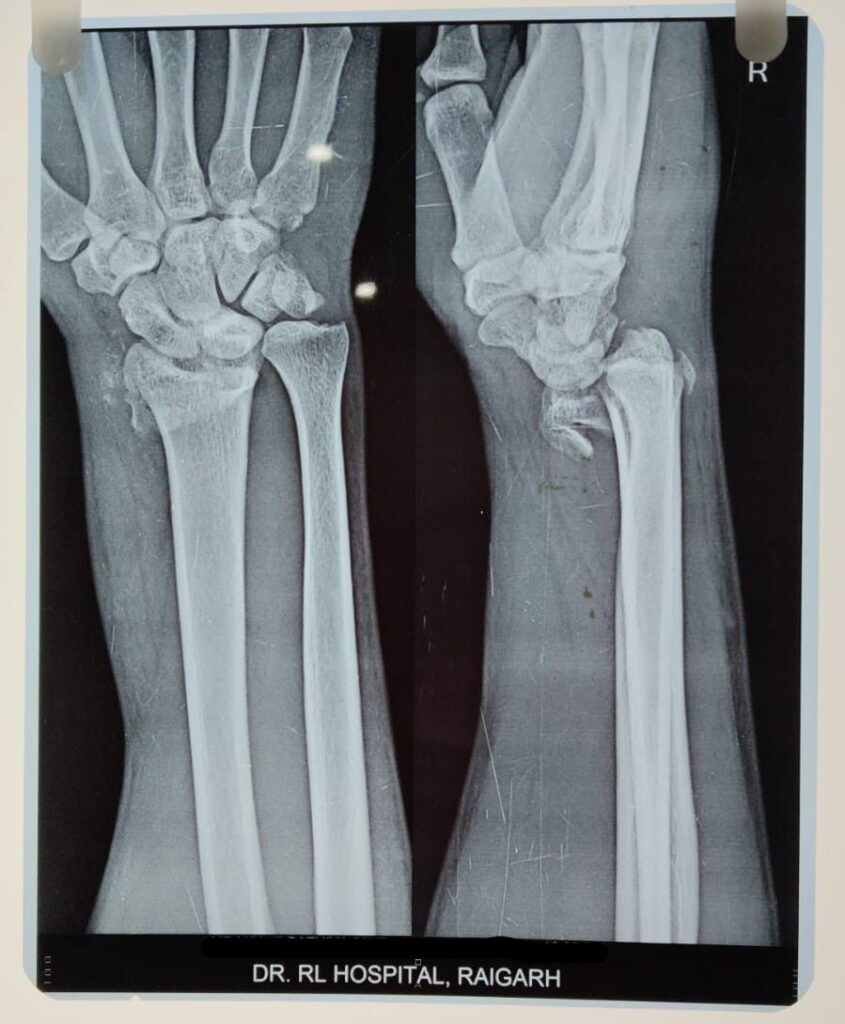

क्या कहते है डॉक्टर…. इस सम्बन्ध में डॉ.आर.एल.हॉस्पिटल के हड्डी रोग विशेषज्ञ डॉ. प्रशांत अग्रवाल ने बताया कि 25 वर्षीय पुरुष नाम न छापने के शर्त पर जो रायगढ़ निवासी है अपने गाँव से बाइक मे जा रहा था सामने से आ रही अन्य बाइक से टकरा जाने से गंभीर रूप से चोटग्रस्त हो गया था, अस्पताल जाँच हेतु आया था। टक्कर की वजह से मरीज का ( डिस्टल रेडियस फ्रैक्चर) हड्डी के कलाई के पास वाला सिरा जो कलाई को गति प्रदान करता है टूट गया था। इसके अलावा (टीबीया फिबुला ) पिंडली की बड़ी हड्डी व पिंडली की छोटी हड्डी जो टीबीया के साथ मिलकर निचले पैर का निर्माण करते है जिसमे टीबीया मुख्य भाग उठाने वाली हड्डी होती है l व फिबुला सहारा देती है दोनों टूट गया था व ( पी. सी. एल.) धागा जो घुटने के पीछे का मजबूत लिगामेन्ट होता है। जो जाँघ की हड्डी (फिमर ) को पिंडली की हड्डी (टीबीया ) से जोड़ता है वह भी टूट गया था मरीज असहनीय दर्द से कराह रहा था। डॉक्टर ने मरीज तात्कालिक जाँच कर भर्ती कराने की सलाह दी। इस तरह के जटिल व मल्टीपल चोट बिना ऑपरेशन के ठीक नई हो पता है। हॉस्पिटल के डायरेक्टर व हड्डी रोग विशेषज्ञ डॉ. प्रशांत ने मरीज के परिजन को सारे शल्य क्रिया के बारे मे बताया व ऑपरेशन हेतु प्रेरित किया। व अस्पताल मे कार्यरत हड्डी रोग विशेषज्ञ डॉ अनंत सिंग के साथ मिलकर मरीज को तीन चरणों मे ऑपरेशन उसे नया जीवन दिया l डॉ. आर. हॉस्पिटल की टीम ने यह मल्टीपल सर्जरी करके मरीज को एक बड़े परेशानी से बाहर निकाला। मरीज अब पूरी तरह स्वस्थ है व चल फिर सकता है।